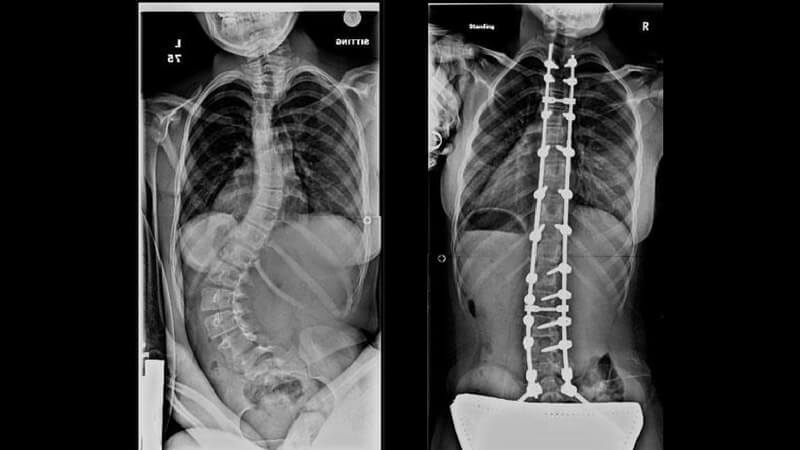

11. The Spine

This photograph is an X-Ray of a patient’s spine who was diagnosed with scoliosis, before and after treatment.